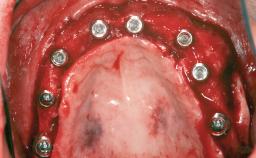

A 47-year-old woman who had suffered from aggressive periodontitis requiring a number of periodontal interventions over more than 10 years was referred by her general dental practitioner and periodontologist for bone augmentation and implant therapy. Her failing dentition had already been scheduled for extraction. The patient expressed a desire for implant-supported fixed restorations and esthetic improvement of her lower face. She had agreed to consult with a maxillofacial surgeon after the referring dentist had suggested bone augmentation. An initial examination by the maxillofacial surgeon revealed mobility of all residual teeth in a patient who was very unhappy with the function of her removable partial dentures. Due to periodontally migrated flaring teeth and loss of occlusal support, the vertical dimension of occlusion was dramatically reduced. The patient was displeased with her lower face because of deepened nasolabial, commissural, and supramental folds.